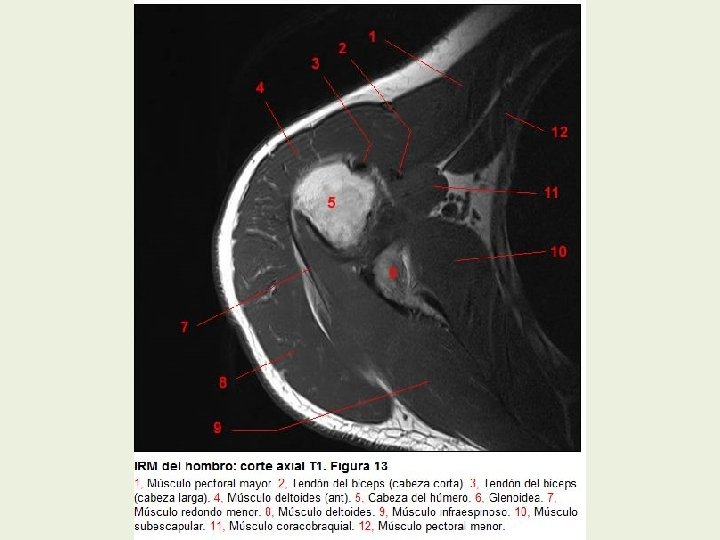

Hombro Cortes axiales RMN